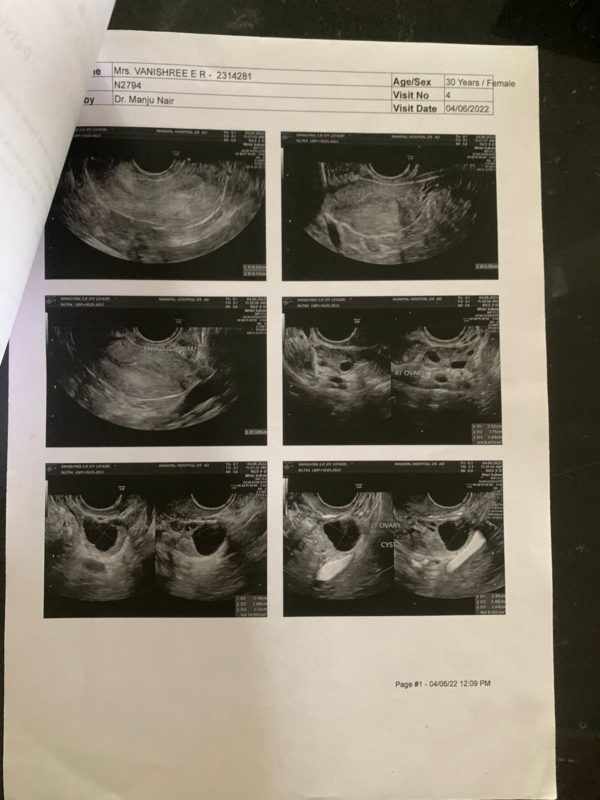

The images of the USG scan shows

2. Post-

Post – Right ovary appeared normal Both fallopian tubes are visualized in their entire length and are normal.